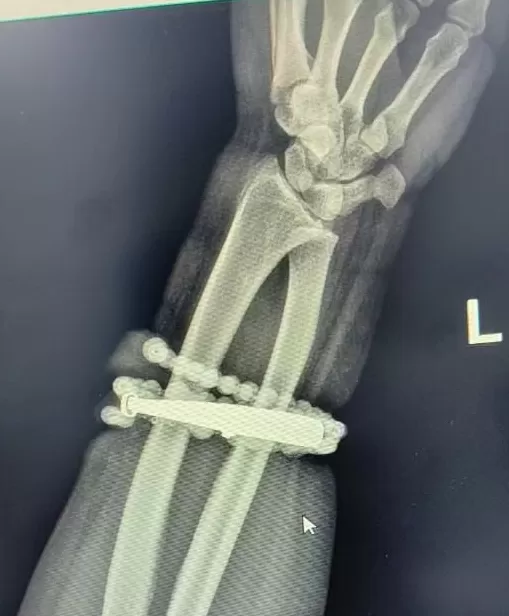

然而,就在两周前,龚女士的情况急转直下:手腕不仅疼痛加剧,还出现了明显的红肿,甚至有脓液渗出。她这才惊觉——手镯和串珠,已经有一部分 " 长 " 进了肉里,根本取不下来了!

" 这是典型的首饰长期压迫、摩擦,加上细菌感染,引发的慢性炎症和肉芽组织增生。" 医生介绍,此时,手镯和串珠已经成了一个不断刺激皮肤、污染伤口的 " 病灶 ",如果不尽快手术取出,感染可能进一步扩散,甚至危及生命或影响手臂功能。

经过一个多小时的手术,医生们将手镯和串珠从厚厚的增生组织中完整剥离出来。目前,龚女士恢复良好,已顺利出院。